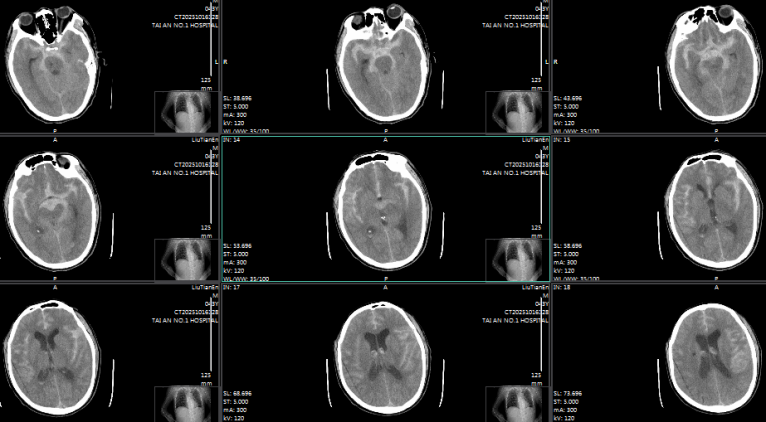

术前颅脑CT

术后颅脑CT

63 岁的女性患者,突发 “剧烈头痛 2 小时” 后被送往医院,颅脑 CT 同样提示蛛网膜下腔出血,CTA 检查高度怀疑右侧大脑中动脉动脉瘤。术中发现,患者右侧大脑中动脉M2分叉处存在两处瘤样凸起:一处为囊性凸起,约2.9mm×2.3mm,瘤颈2.1mm;另一处更大,呈椭圆形,大小约14.3mm×9.0mm,瘤颈6.5mm,瘤体右外侧见子瘤且累及下干,病情更为复杂凶险。